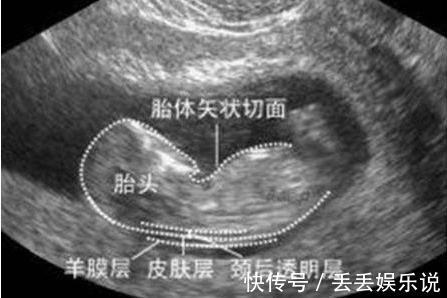

在孕期11~14周之间做的检查,早唐+NT其实是两项不同的检查,早唐是抽血检查,而NT是B超检查,之所以合并在一起,是因为检查的时间非常相近。

这次检查一定要在孕期14周前完成,否则胎儿颈部透明带消失,就无法进行检查了。

孕妈在NT检查前可以带一些食物,因为NT检查需要胎儿呈现特定的姿势才能看清,在检查中适当进食,可以促进胎儿移动,帮助调整最佳的姿势。